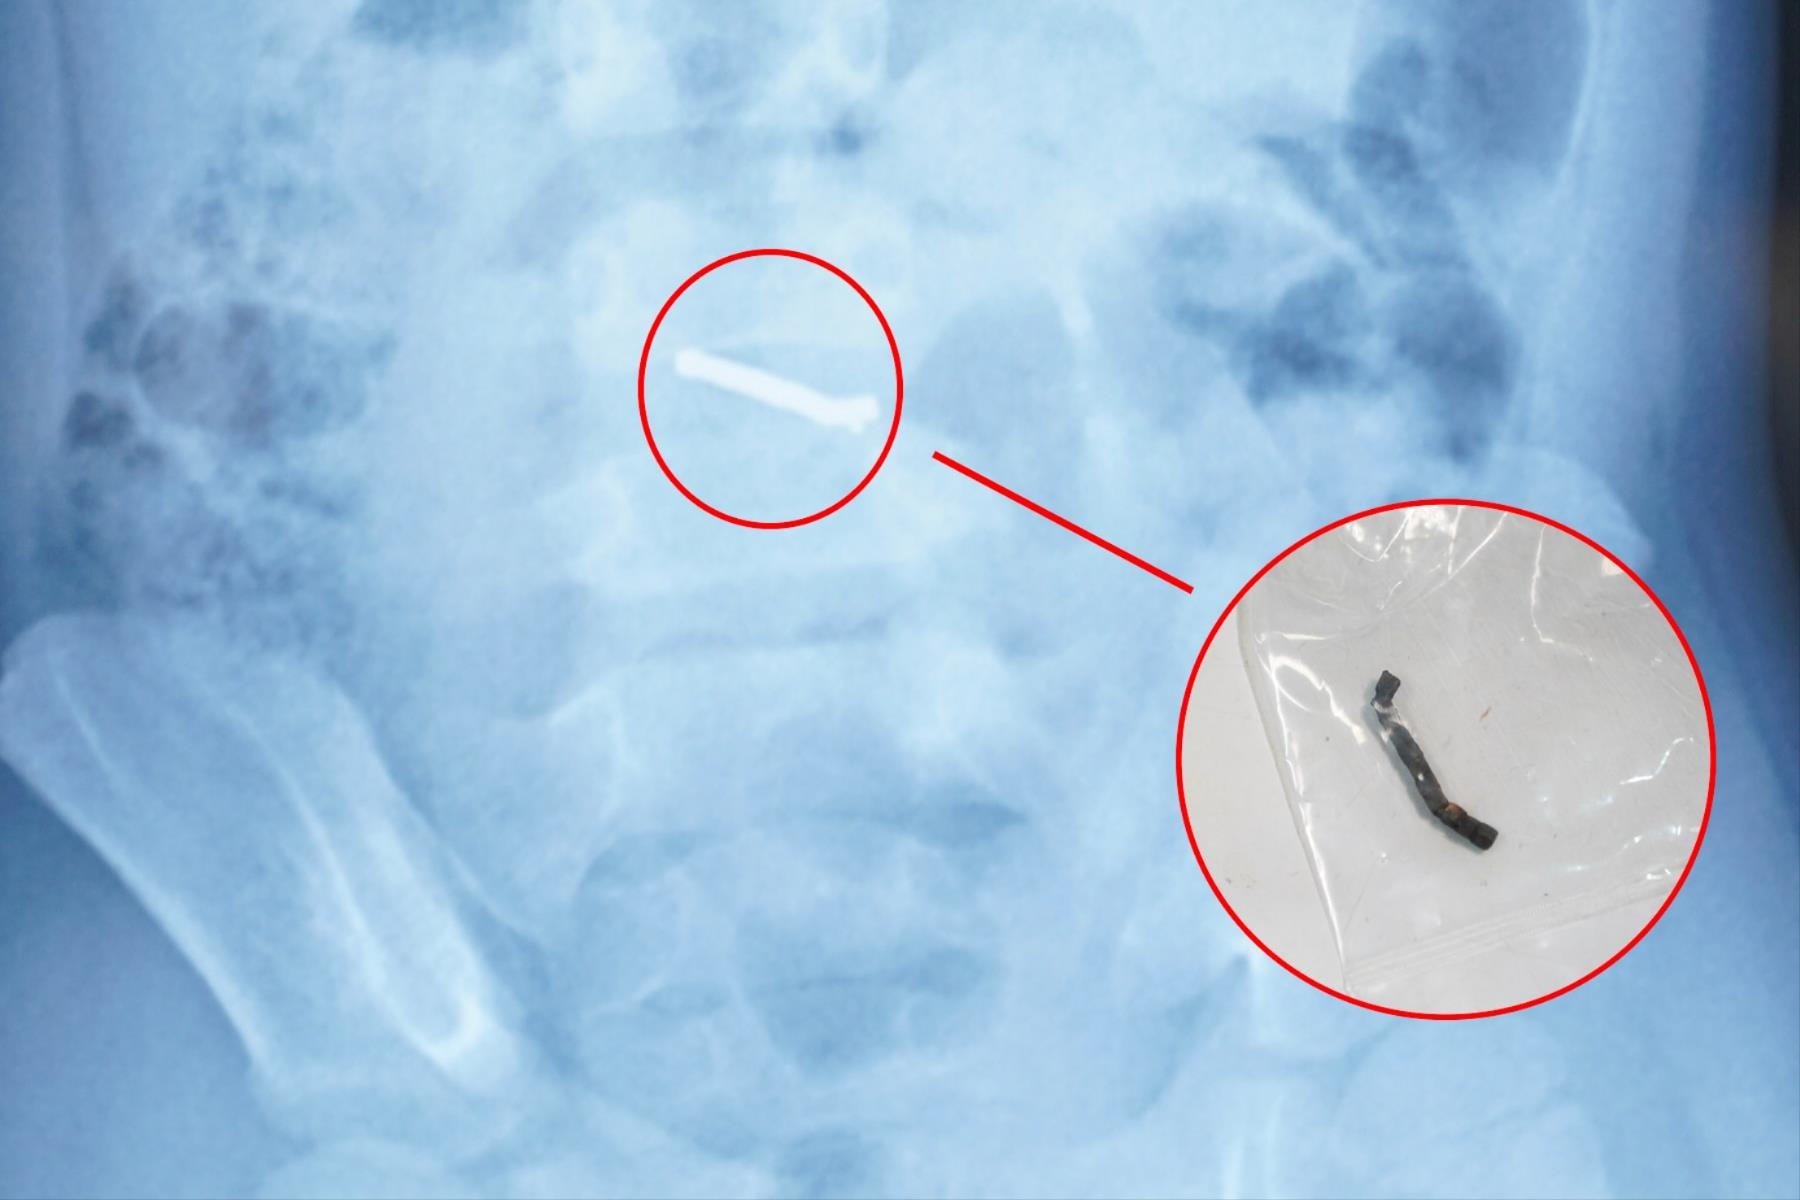

Bé trai 5 tuổi thủng ruột vì nuốt nam châm

(CLO) Các bác sĩ tại Bệnh viện Nhi Trung ương vừa phẫu thuật thành công cho một bé trai 5 tuổi sau khi phát hiện nhiều dị vật nam châm trong ổ bụng, gây thủng ruột nguy hiểm.